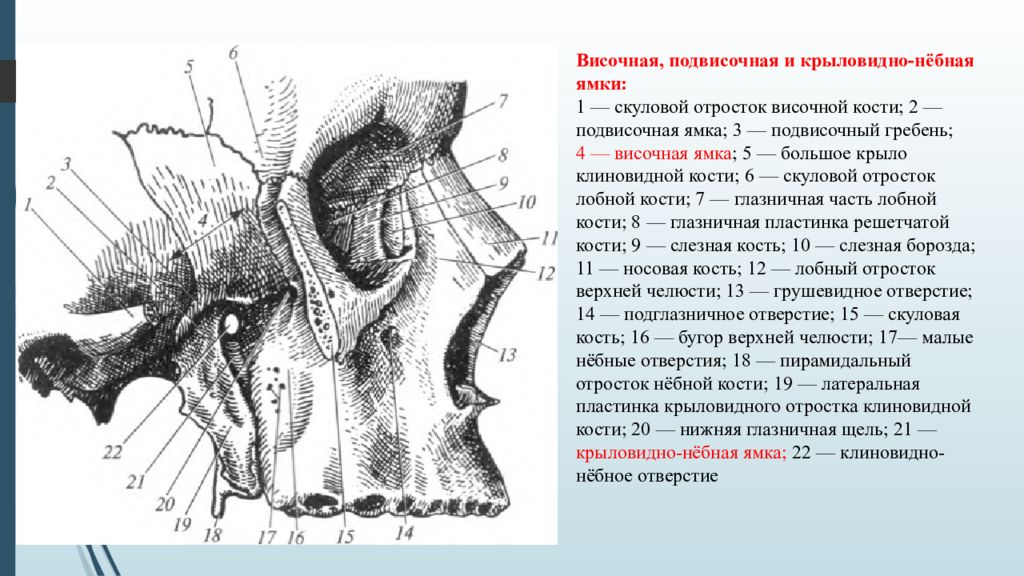

Анатомические особенности: фотографии ямок черепа, височной и подвисочной крылонебной